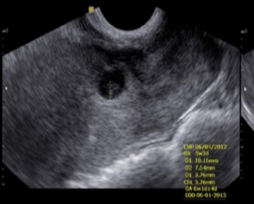

C-section ectopic